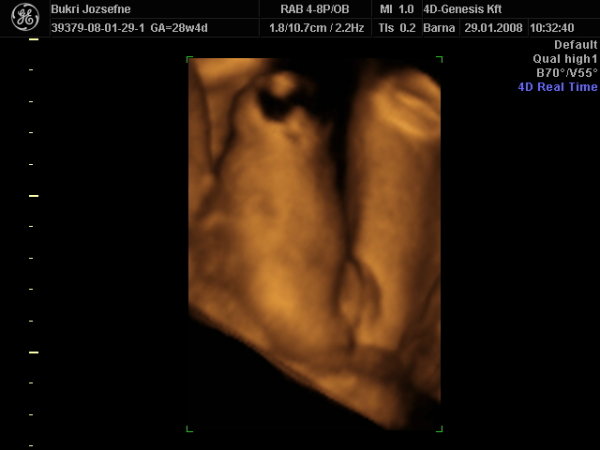

Tudom nagyon rég jártam erre de van a pici puncisunkról képeim és megszeretném nektek mutatni bár nagyon nem akarta megmutatni a lába közét ismét teljesen a 4d-n de nem adta fel a szonográfus és 40 perc után a kicsi lány terpesztett egyet és így már biztire tudjuk a nemét is.A neve még kérdéses !

Milyen hamar eltelt az idő nemsokára babázni fogsz és igaz kixcsit messze van nekem az április de én is nem sokára. Kép lányunk Kép lányunk Ez már bizonyíték!!!